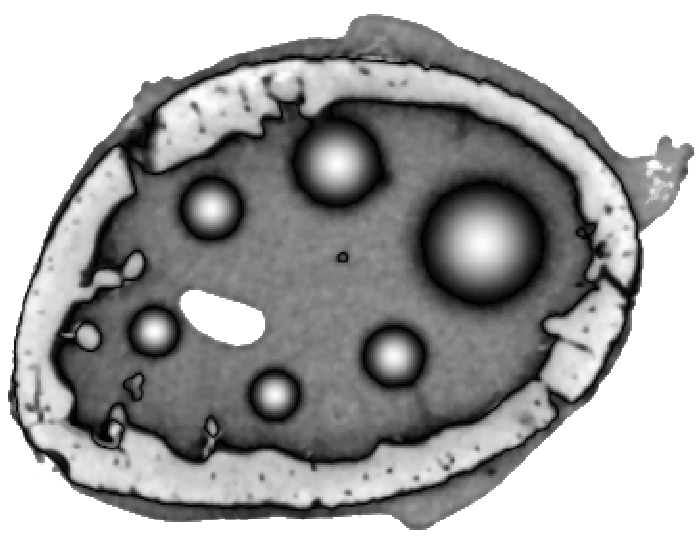

To simulate emission tomography reconstruction we designed a more realistic phantom from the high-quality X-ray scan of a mice bone. The data was acquired on a Nikon Metris Custom Bay cone-beam scanner at the Henry Moseley Manchester X-ray facility, and was reconstructed with the Feldkamp algorithm (see Fig. 7 (left)). We thresholded the obtained reconstruction and added six gaussians with various kernel widths (see Fig. 7 (middle and right)).

To simulate PET projection data we used NiftyRec [22], a software for tomographic reconstruction, providing GPU-accelerated reconstruction for emission and transmission computed tomography. The phantom size is pixels and 300 projections was simulated. Poisson noise was added to projections with an expected number of photon counts in total. Twenty noise realizations were simulated to estimate methods quantitatively. The point spread function of the PET system was modelled (with convolution of the sinogram columns with a Gaussian of full width half maximum of three pixels) in the projection and back-projection operations. No scatter was simulated in this study. For our experiments (see algorithm 2) we performed 130 MLEM iterations and 5 inner iterations (denoising step).

To quantify obtained reconstructions we used averaged over all noise realizations RMSE (23) values in the bone region (BR) and in Gaussian regions (GR). All regularization parameters were carefully selected by comparing the mean of all RMSE values over all noise realizations in GR and BR (see Fig. 8).

After estimation of regularization parameters we performed twenty reconstructions for each method with various Poisson noise distributions. The mean values for GR and BR over all noise realizations are shown in Fig. 9. This result proves that the EL penalty is very successful in resolving smooth features (six Gaussians in this case) and also quite competitive for the BR (lower RMSE value than for TV).

In Fig. 10 and 11 one can notice that the BR is very smooth for TV and TV- penalties and some long-wave oscillations can be seen in the reconstructed image with EL penalty. This result corresponds to the expected behaviour of the EL penalty. We note here that the phantoms background (see Fig. 7) is not as flat as TV and TV- penalty recovered it. Furthermore, a small size dot-like feature (approximately in the centre of the phantom) is almost smoothed out with TV and TV- recovery. However, it is visible and well recovered with EL penalty. The sharp features, overall, are reconstructed very well with MLEM-EL method and seem even sharper compare to other methods (see the bone outer rim in Fig 10).